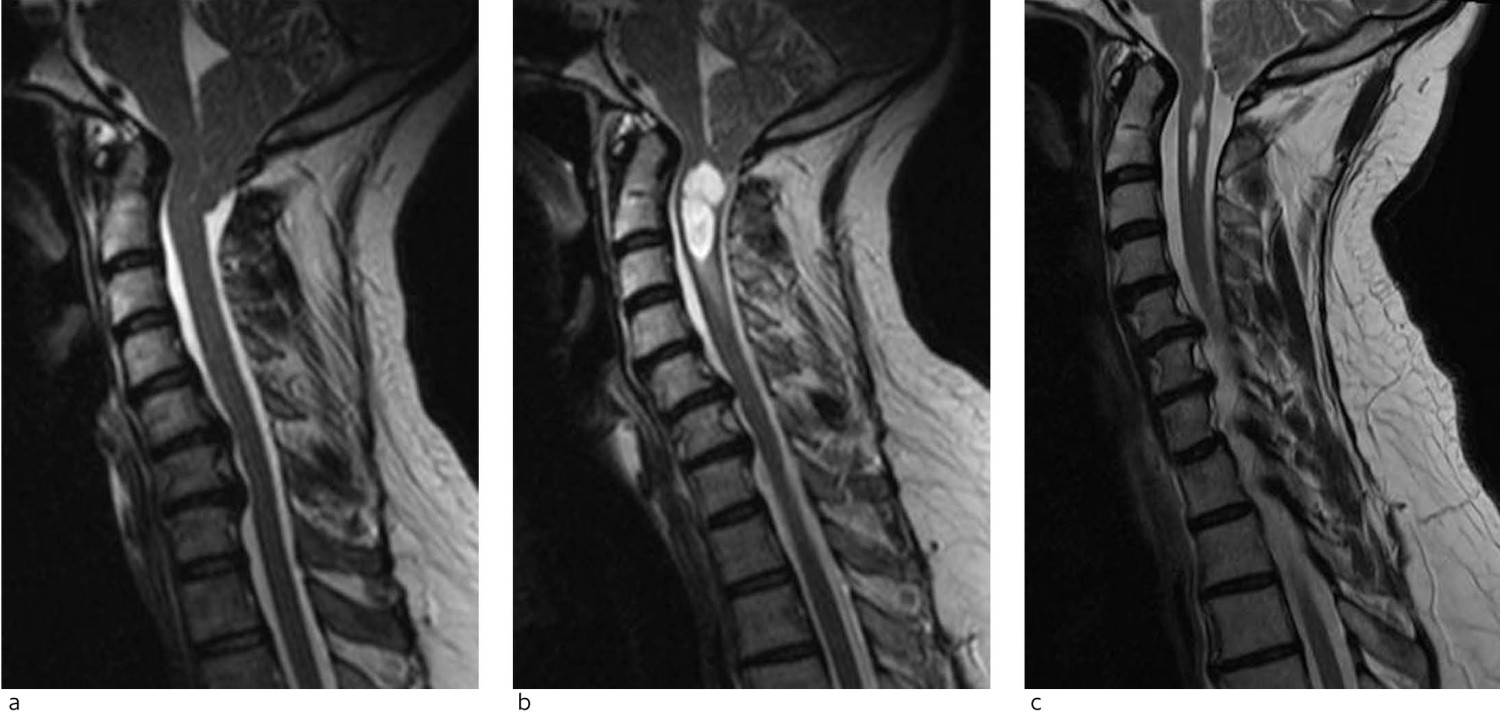

Ved «klassisk» Chiari-malformasjon type 1, der problemet anses å være trange forhold i foramen magnum grunnet tonsillær ektopi, er den kirurgiske behandlingen dekompresjon av foramen magnum, også kalt occipito- eller kraniocervikal dekompresjon, hvilket imidlertid antyder en mye større operasjon enn det som egentlig er tilfelle.

Målet med inngrepet er å skape bedre plassforhold i den kraniocervikale overgangen ved å utføre en liten kraniektomi ovenfor foramen magnum, laminektomi av C1 og vanligvis også ekspanderende duraplastikk (figur 3). Kun i enkelte tilfeller må det utføres reseksjon av ektopiske lillehjernetonsiller, hvis disse er så voluminøse at de hindrer tilstrekkelig dekompresjon. Etter vellykket operasjon blir cisterna magna rekonstruert og passasje av spinalvæske gjennom foramen magnum gjenopprettet. Risikoen ved inngrepet er lav. Den vanligste komplikasjonen er submuskulær/subkutan spinalvæskeansamling (pseudomeningocele), kun unntaksvis med åpen lekkasje fra såret og som regel med spontan restitusjon.

Det er viktig å poengtere at syringomyeli, som ved Chiari-malformasjon type 1 er konsekvens av trange forhold i foramen magnum, i de aller fleste tilfeller vil minske eller stabilisere seg spontant etter dekompresjon alene (figur 3). Det er dermed vanligvis ikke nødvendig med direkte inngrep mot syrinx. Åpning eller drenering av syrinx (syringo-subaraknoidal eller -pleural shunt) utføres kun i ytterst sjeldne situasjoner hvor syringomyeli progredierer radiologisk eller klinisk selv etter tilfredsstillende dekompresjon av foramen magnum.